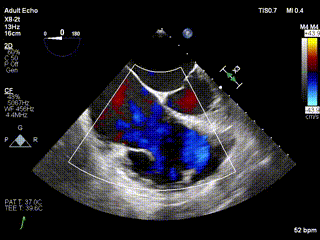

三例患者入院后,葛均波院士團隊周達新教授、潘文志教授、張源博士、陳莎莎博士及心超室的潘翠珍教授、李偉教授對患者的情況進行詳細評估和討論,最終決定為三例患者選擇LuX-Valve Plus40mm、50mm和50mm型號的瓣膜進行手術治療。手術后即刻拔除氣管插管,術后患者三尖瓣反流癥狀得到顯著改善,復查心超結果顯示人工三尖瓣瓣膜支架固定穩(wěn)定,瓣葉關閉形態(tài)未見異常,未見明顯反流。